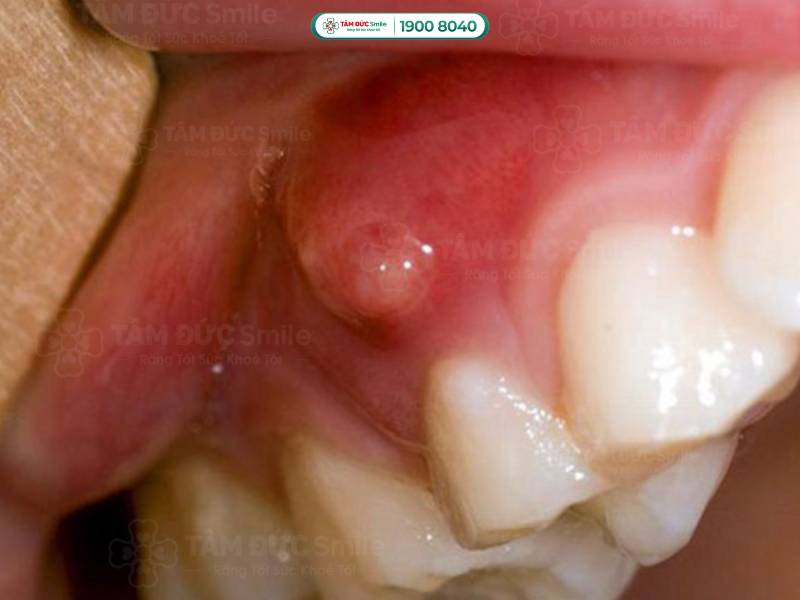

1.1.2. Áp xe chóp răng (áp xe chân răng)

Áp xe được hiểu là tập hợp mủ được hình thành từ các tế bào bạch cầu chết, vi khuẩn và những mảnh mô vụn. Vấn đề áp xe chóp răng bắt đầu từ tủy răng và kết thúc ở phần chóp chân răng.

Vấn đề áp xe chóp răng bắt đầu từ tủy răng và kết thúc ở phần chóp chân răng

Phần lớn các trường hợp áp xe chân răng là do sâu răng, răng bị sứt mẻ nặng gây tổn thương tới tủy. Ngoài ra, người bệnh viêm nướu, viêm nha chu cũng có nguy cơ bị áp xe chóp răng cao hơn. Bởi vì vi khuẩn phát triển dần vào chóp răng, gây viêm nhiễm, theo thời gian tiến triển thành áp xe.

► Biến chứng do áp xe chân răng

Áp xe chân răng khiến người bệnh đau đớn kéo dài, ăn uống không ngon miệng. Do đó, sức khỏe người bệnh nhanh chóng giảm sút. Về lâu dài, ổ áp xe sẽ làm răng bị rụng, mất răng.

Chứng áp xe chóp răng thường khó nhận biết bằng mắt thường. Người bệnh có những biểu hiện dưới đây nên đến thăm khám ở các cơ sở y tế để được chẩn trị chính xác:

- Đau nhức răng, người bệnh chỉ cần nhai nhẹ cũng có cảm giác đau.

- Ê buốt răng khi sử dụng các loại thực phẩm nóng, lạnh.

- Vùng áp xe có thể làm hành sốt, nổi hạch ở cổ, khiến người bị mệt mỏi.

- Phần lợi dưới chân răng bị sưng; khi soi gương, bạn có thể thấy hạt mủ tụ ở phần chân răng gây đau.